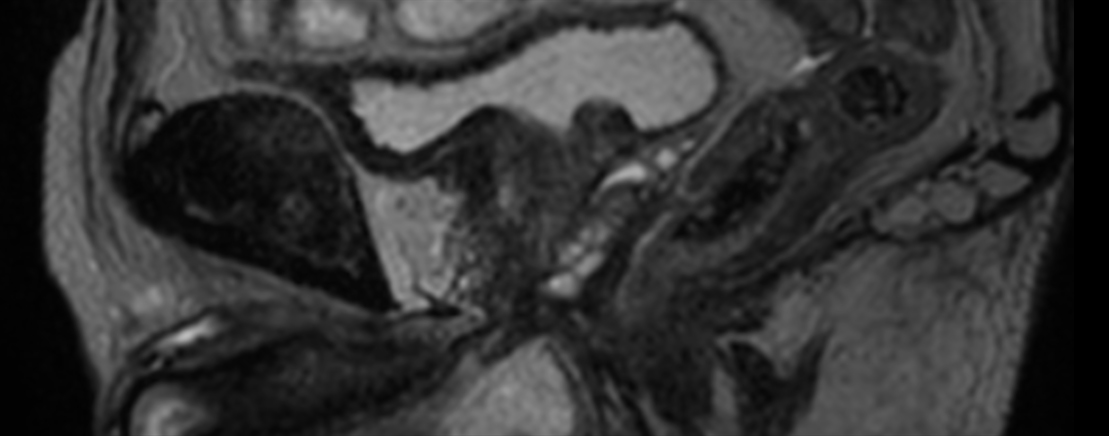

Coronal T2w TSE FatSat